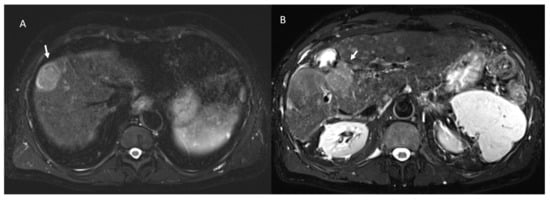

- 21 showed APHE and 2 rim APHE during arterial Phase (Figure 2).

- 23 showed wash-out appearance during portal phase and hypointense SI in equilibrium phase (Figure 2).